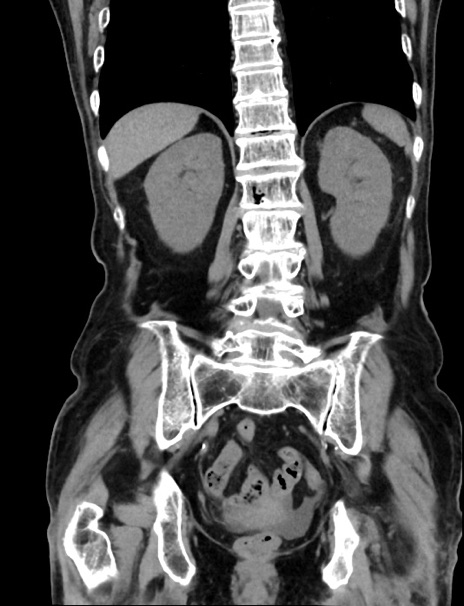

症例33(冠状断像)

【症例】70歳代 女性

【主訴】心窩部痛

【現病歴】延髄病変の精査・加療にて神経内科入院中。本日より心窩部痛あり。

【身体所見】右下腹部を中心に圧痛と反跳痛あり。

【データ】WBC 10900、CRP 0.02